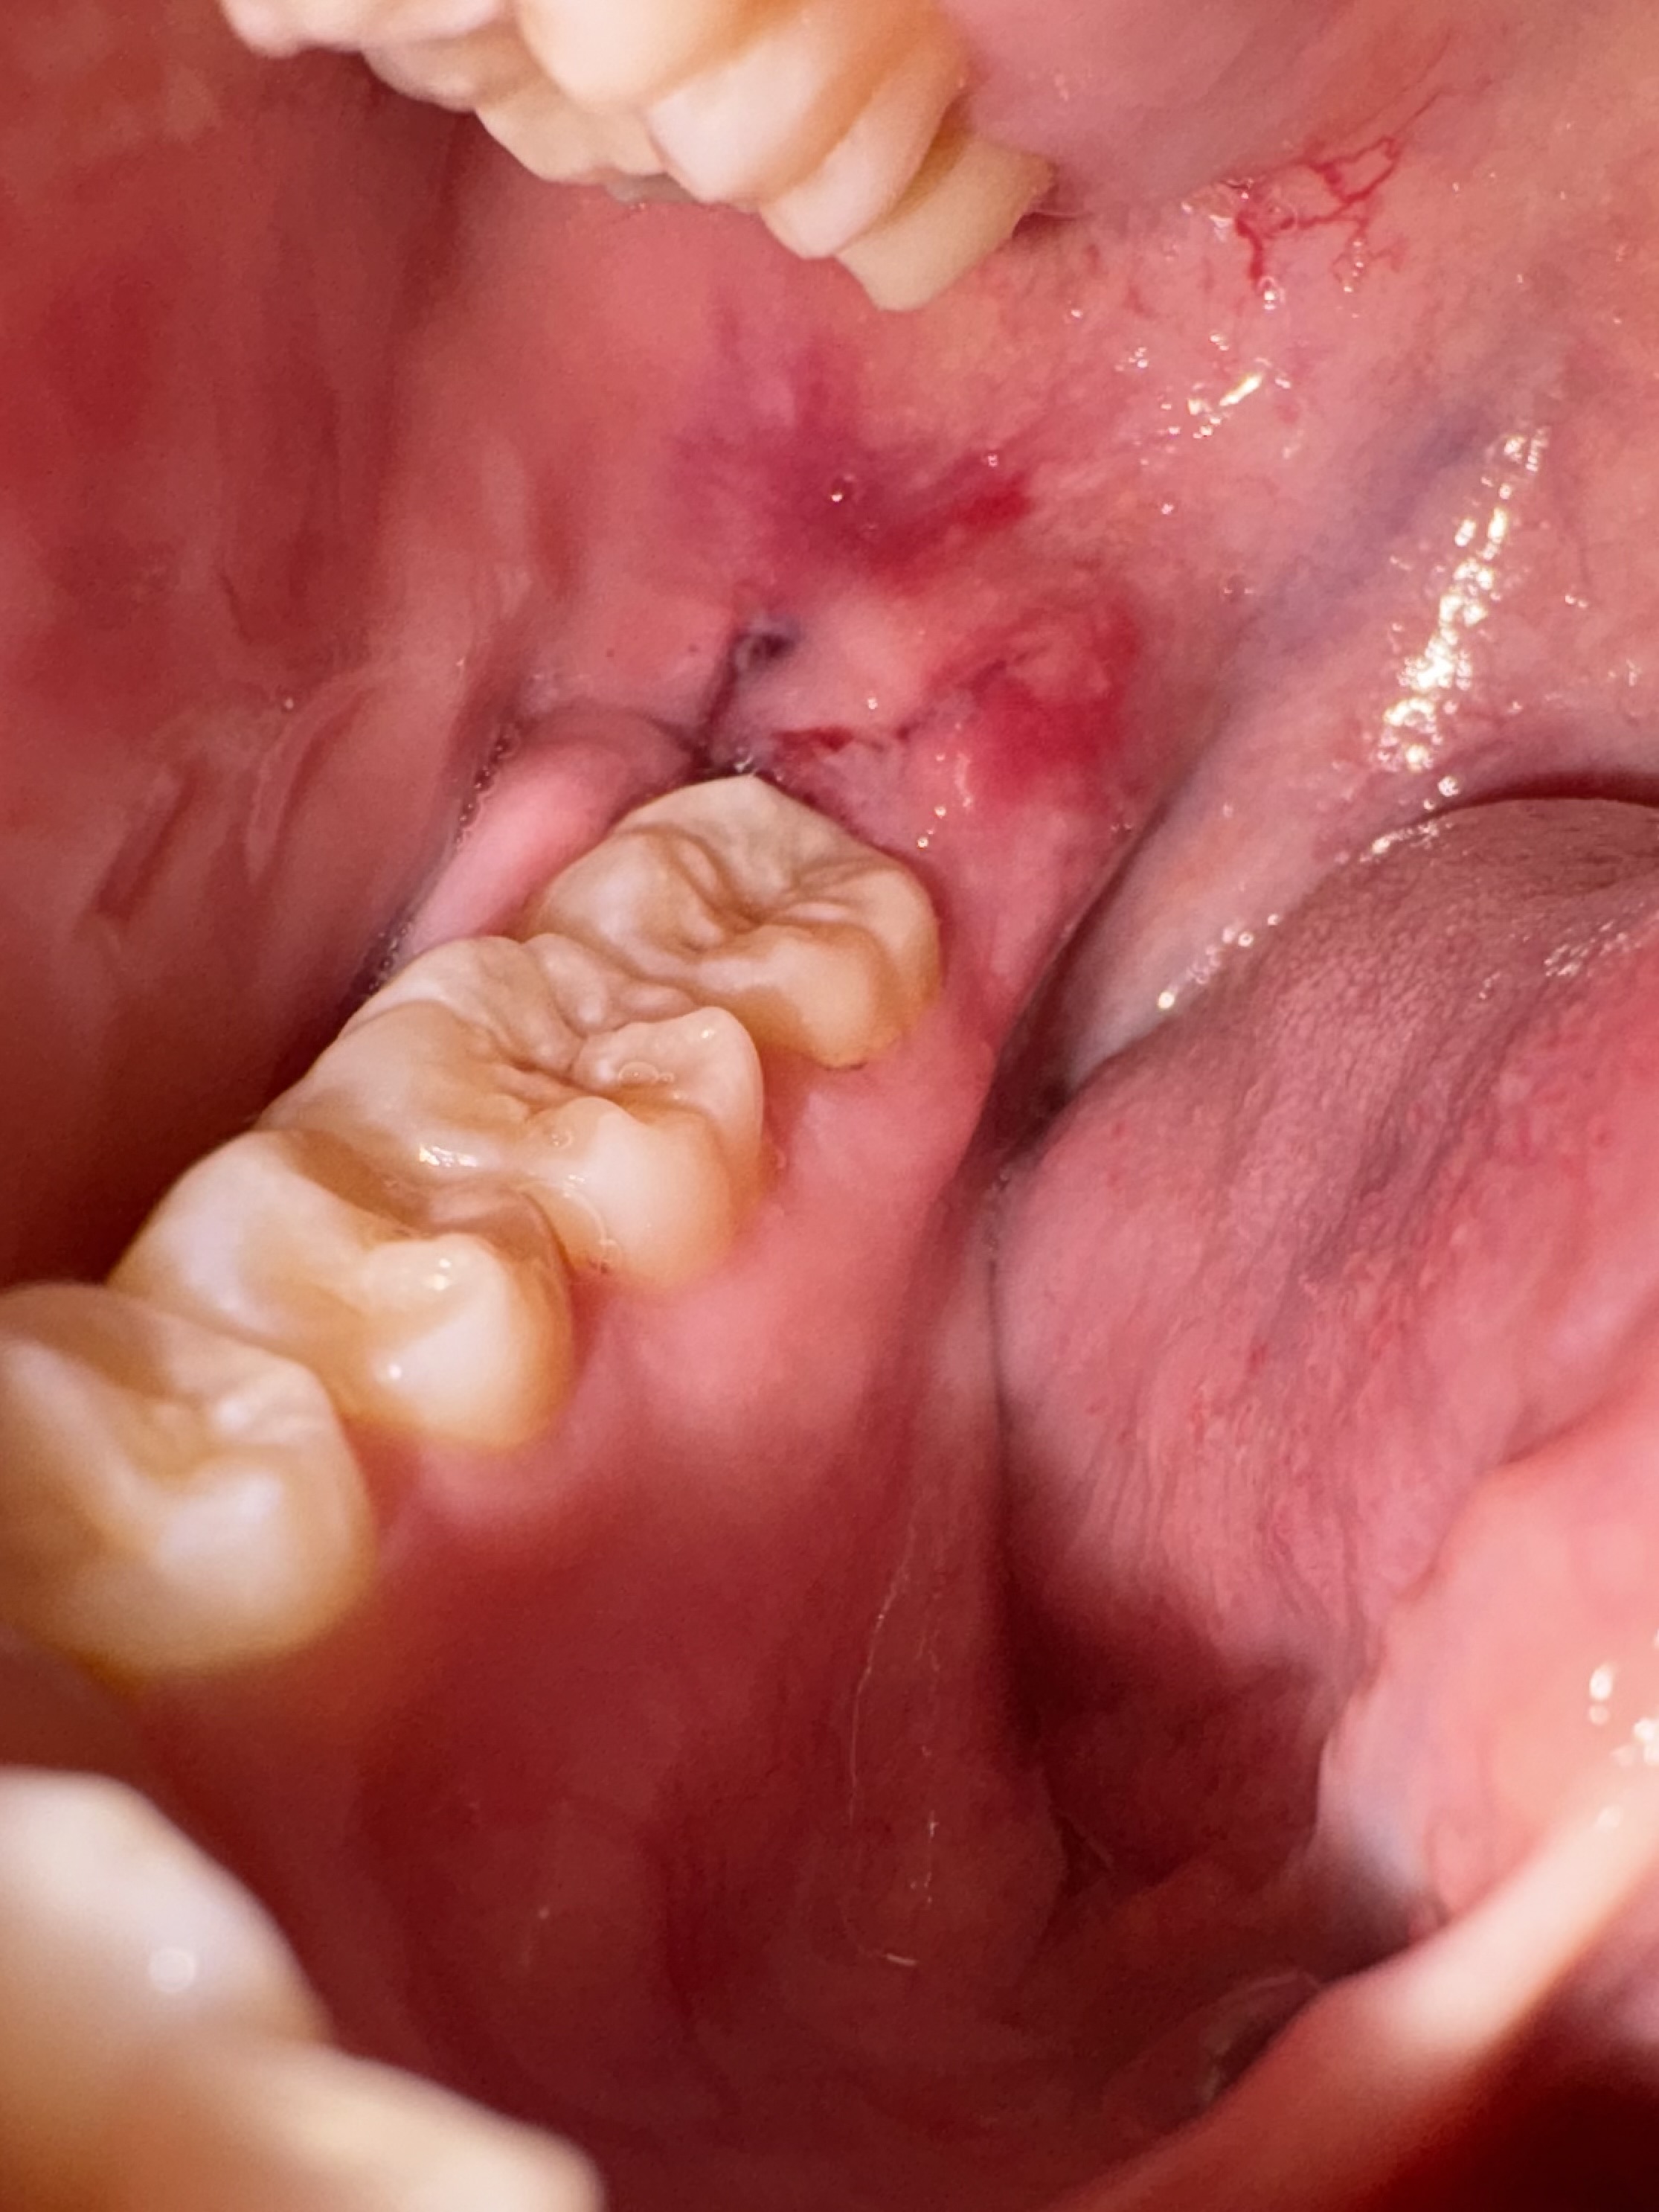

智歯周囲炎でレーザー治療しましたが、歯茎の腫れが引きません。

回答数:2 -